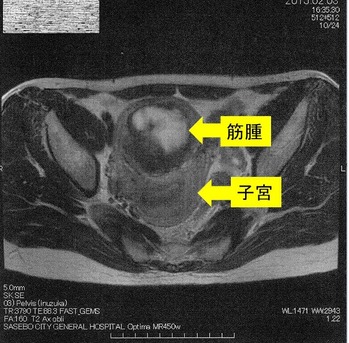

´ÁÊýÌô¤Ç»ÒµÜ¶Ú¼ð9Ѥ¬7ѤËÀ¸ÍýÄˤâ¿Î̽зì¤â²þÁ±¼ê½Ñ²óÈò¤Ç¤¹¡£¶Ú¼ð¤ÎMRI¼Ì¿¿¤Ç¤¹

¡Ú2015ǯ2·î3Æü¡¡£Í£Ò£É¼Ì¿¿¡Û

¢¨Çò¤¤Éôʬ¤¬¶Ú¼ð¡¢¼þ¤ê¤ÎÉôʬ¤¬»ÒµÜ¤Ç¤¹¡£